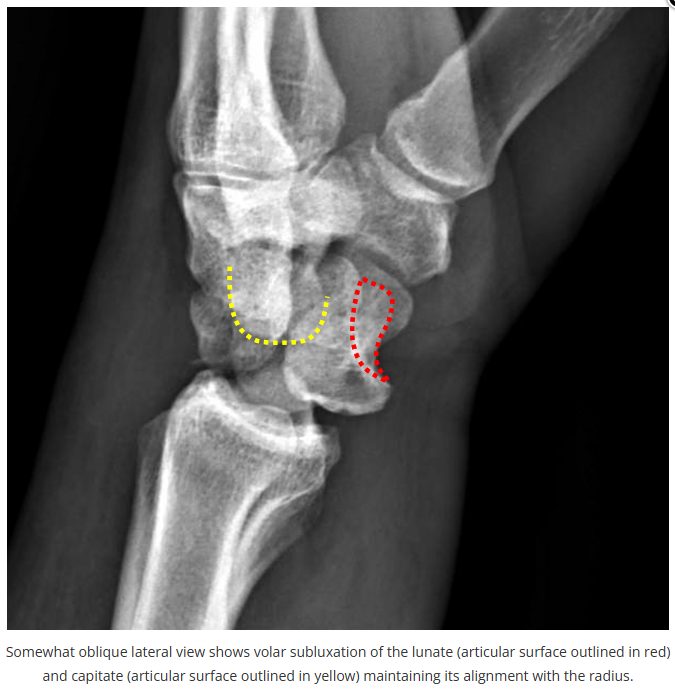

今天是腕部与手的X线片。所有X线片都

带有标注和说明

,可以选择长按图片,

自动翻译相关说明